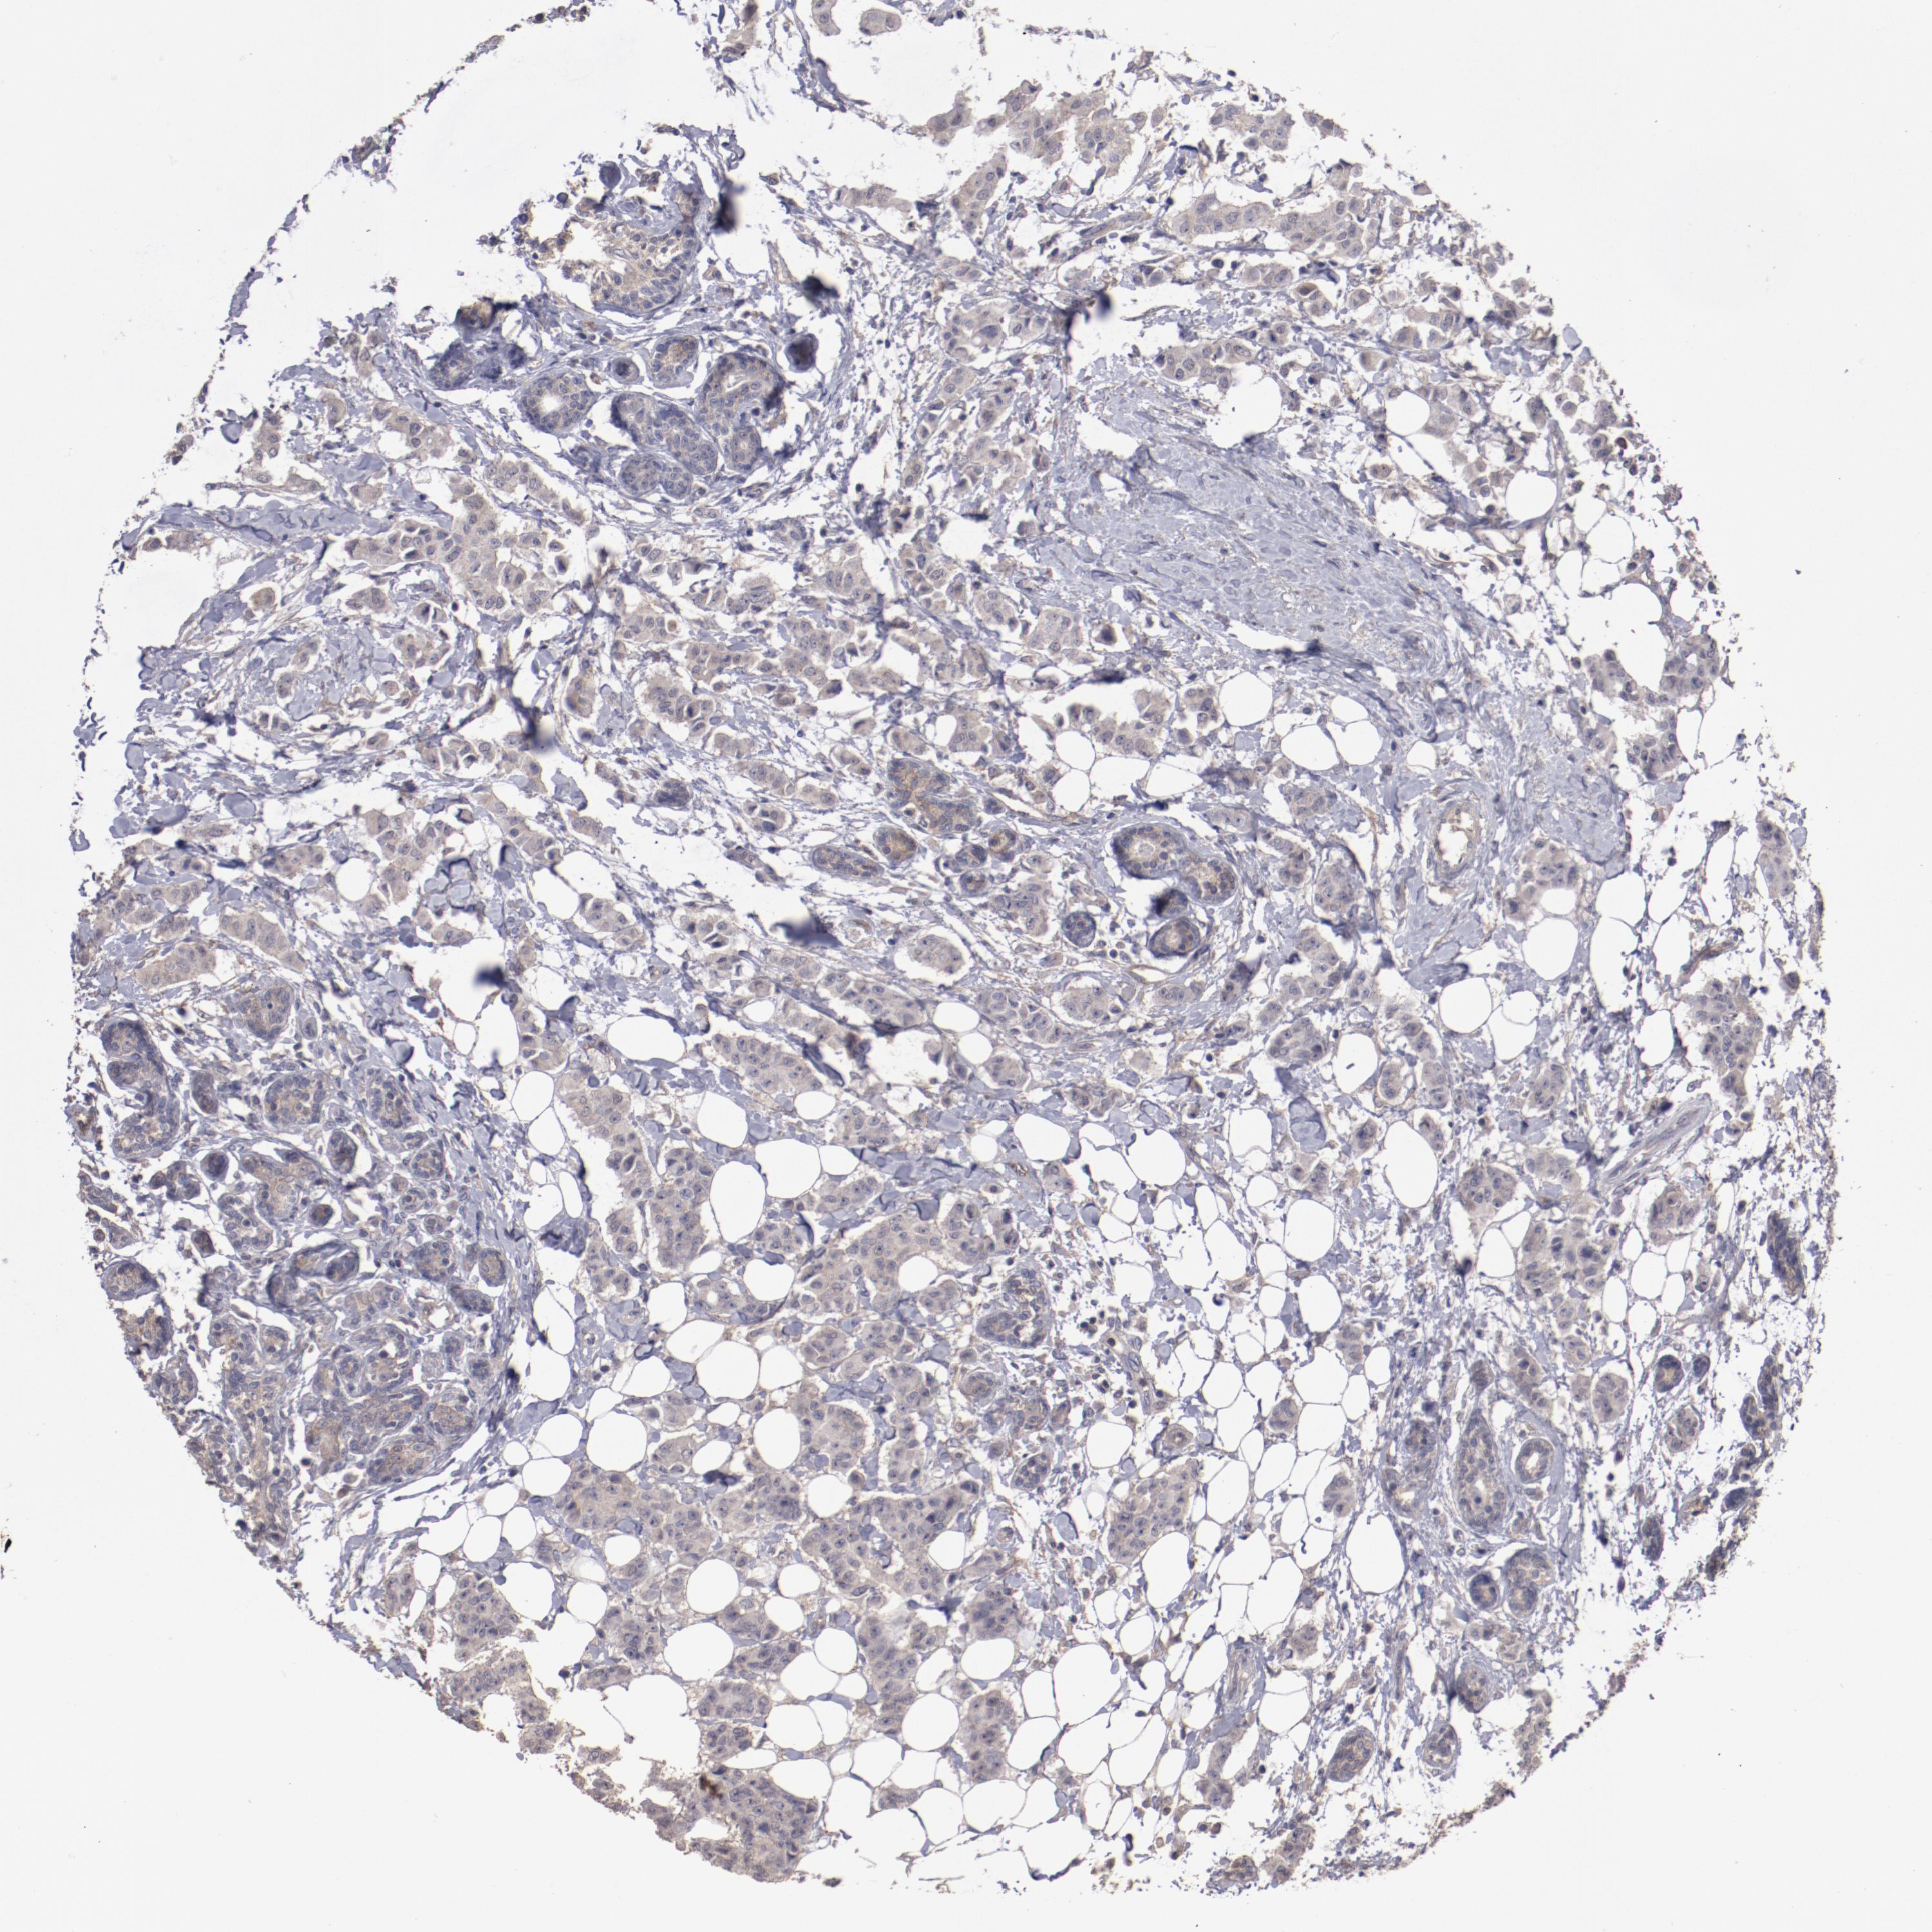

CANCER BREAST CANCER Show tissue menu

BRCA TCGA BRCA VALIDATION PROTEIN EXPRESSION